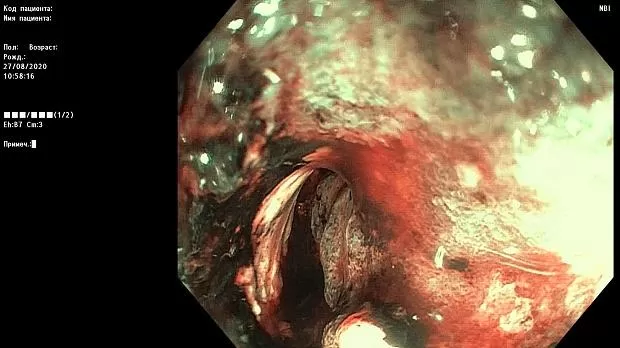

Краткое описание эндоскопической картины.

В проксимальной части сигмовидной кишки имеется асимметричное циркулярное сужение за счет плотной бугристой ткани, с признаками ригидности, структура поверхности и сосуды не визуализируются.

Просвет опухолевого канала 1 см, определенная протяженность — около 10 см. Патогистологическое исследование № 1455-62 от 28.08.2020 г.

Макроскопическое описание: Серовато — коричневых кусочков размером 0,1 — 0,2 см.

Микроскопическое описание: фрагменты представлены соединительнотканной стромой, в которой определяется рост криброзных и железистых структур, сформированных анаплазированным эпителием с крупными гиперхромными ядрами с выраженным полиморфизмом, отмечаются фигуры митозов; местами с поверхности кусочков сохранена выстилка типичным кишечным эпителием